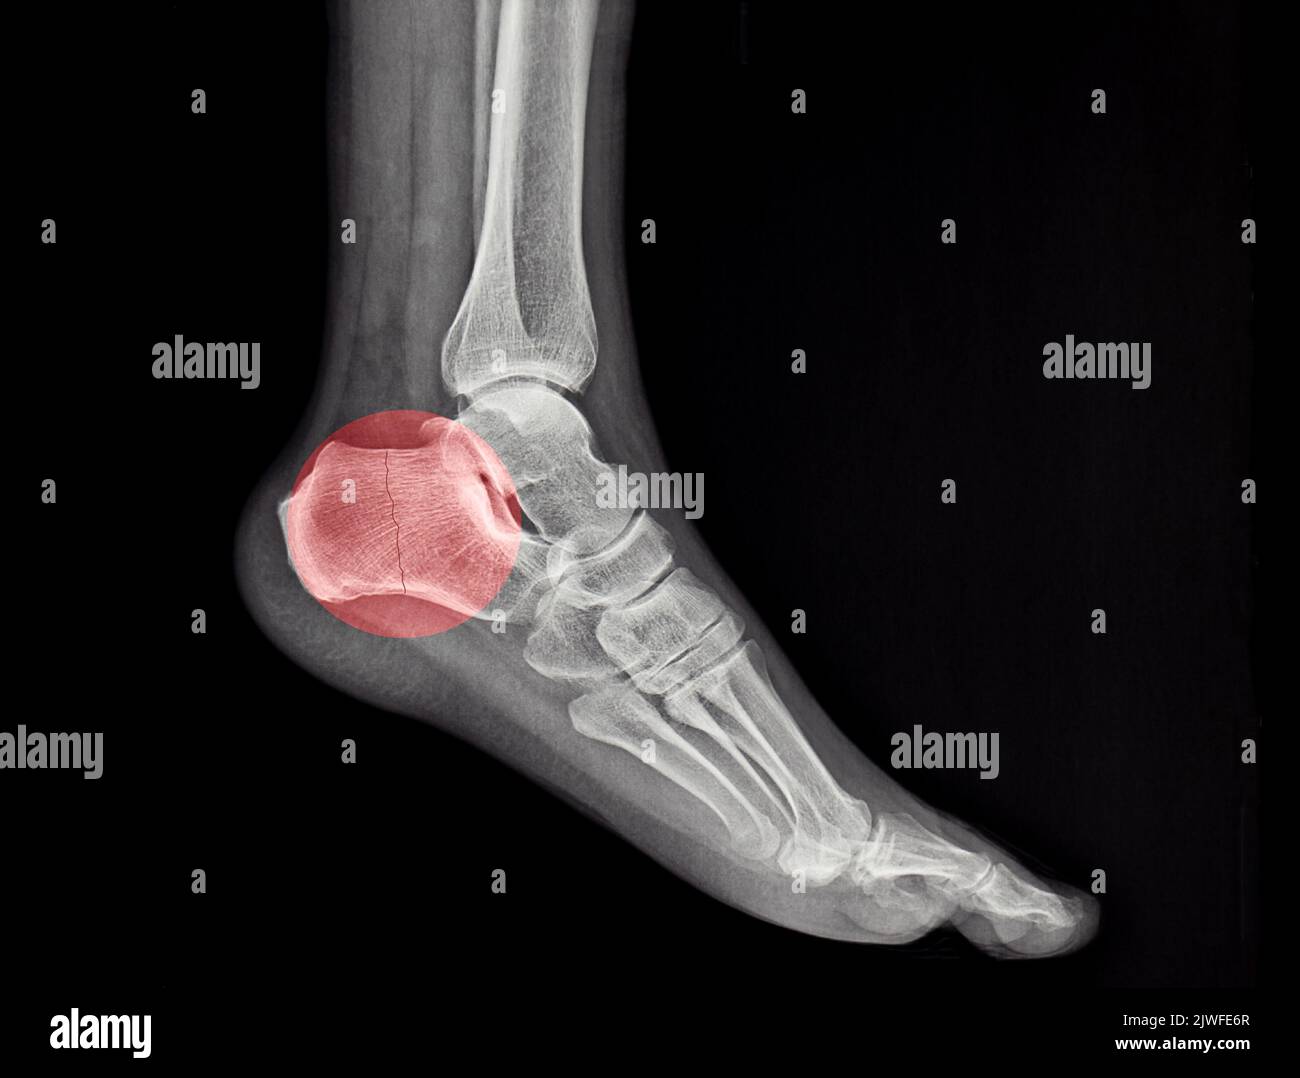

XRay Image Of Ankle, Lateral View. Showing Heel Fracture. Stock Photo Heel Fracture X Ray You might feel throbbing pain and see blisters. This series provides a two view investigation of the calcaneus. These fractures often occur because of. A calcaneal stress fracture is one or more small breaks in your heel bone (calcaneus). Calcaneus fractures are the most common fractured tarsal bone and are associated with a high degree of morbidity and disability. If. Heel Fracture X Ray.

Fractured Heel, Xray Stock Image C027/2614 Science Photo Library Heel Fracture X Ray The calcaneus is the most commonly fractured tarsal bone accounting for ~60% of all tarsal fractures 1. The calcaneus axial view is part of the two view calcaneus series assessing the talocalcaneal joint and plantar aspects of the. A calcaneal stress fracture is one or more small breaks in your heel bone (calcaneus). If you break your calcaneus, it usually. Heel Fracture X Ray.